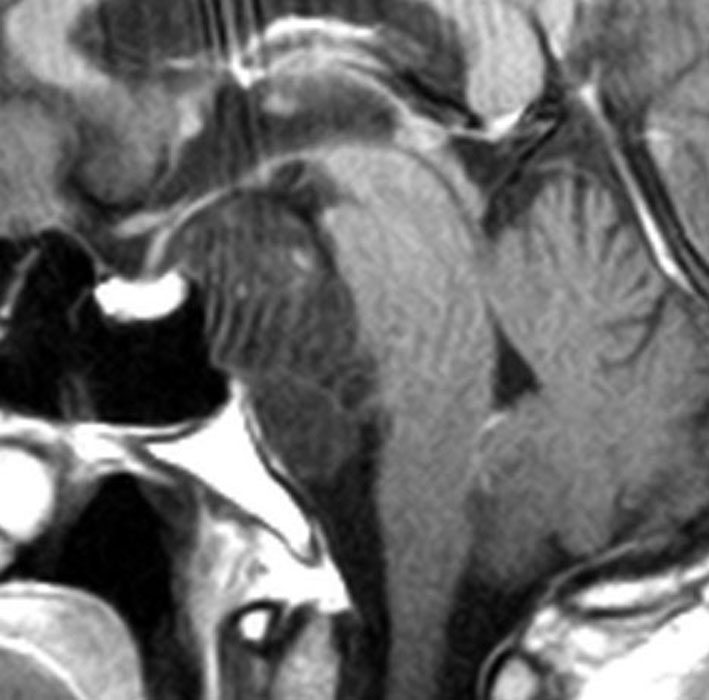

斜台の脊索腫 classical type

CTでは,斜台から左蝶形骨にかけて不規則な骨破壊像がみられます。

MRI T2強調画像(左)では等信号から高信号のまだらな境界が不明瞭な腫瘍が斜台から左海綿静脈洞内に浸潤しているのがみられます。T1強調ガドリニウム増強では,腫瘍がまだらに増強されています。トルコ鞍から鞍上部に伸び,視交差を侵し第3脳室底まで伸展しています。脊索腫が硬膜内に浸潤して神経組織と癒着することは珍しいことではありません。